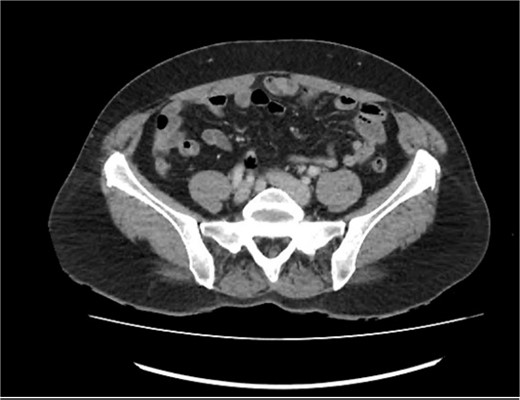

Owing to the persistence of RIF pain and CT evidence of appendicitis, the provisional diagnosis of chronic appendicitis was made, and the patient was referred for laparoscopic appendicectomy. An appendicetomy was performed 5 days following the initial referral. Intra-operatively, the appendix was injected and thickened with an oedematous mesoappendix. The patient recovered well and was discharged following the operation. Histopathology demonstrated the appendix measured 70 mm x 12 mm x 12 mm with the attached mesoappendix measuring 70 mm x 25 mm. The lumen of the appendix was filled with gelatinous material. A neoplastic lesion was noted in the proximal 2/3 of appendix, measuring 45 mm, and was classified as a LAMN, with American Joint Committee on Cancer staging of pT3N0MX. One mesoappendiceal lymph node demonstrated no evidence of malignancy. A two-month follow-up colonoscopy was unremarkable and demonstrated no polyps, as revealed in Fig. 2. Follow-up CT chest and abdomen/pelvis demonstrated no evidence of metastases. Tumour markers were normal, with carcinoembryonic antigen (CEA) <1.7μg/L, CA-199 10U/ml and CA-125 22U/ml.Due to the finding of LAMN, opinions were sought through multidisciplinary team meetings (MDTs) with medical and surgical oncologists. Additionally, opinions from peritonectomy teams were obtained. The MDT concluded that based on the LAMN confinement to the appendix, the risk of future pseudomyxoma peritonei (PMP) was low, and the patient did not require further surgical intervention. An additional opinion regarding histology was obtained, which determined the specimen was in most keeping with an appendiceal diverticulum rather than a LAMN, supporting the decision that no further treatment or surgical resection was required.

Colonoscopy performed 2 months following appendectomy demonstrating no abnormalities.